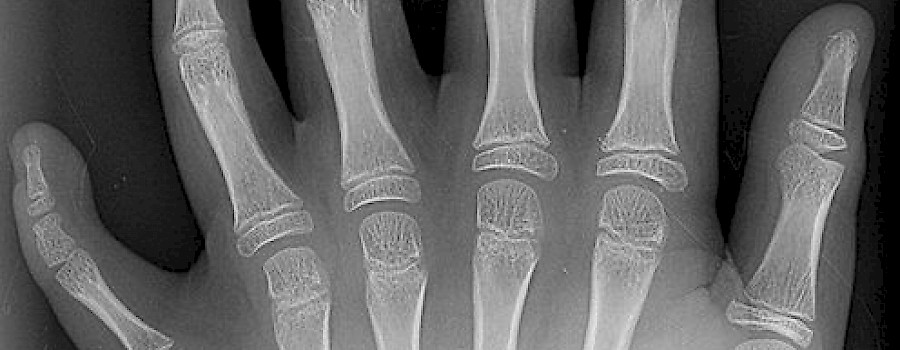

Röntgen trotz Schwangerschaft

Wird eine schwangere Frau einer Bestrahlung ausgesetzt, dann kann es bei dem ungeborenen Kind zu Fehlbildungen und Entwicklungsstörungen kommen. Zudem besteht für das Kind ein erhöhtes Risiko, an Krebs oder Leukämie zu erkranken.